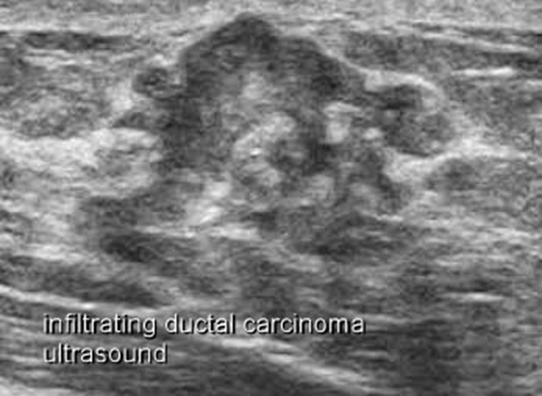

Malignant-

- irregular indistinct outline,

- hypoechoic due to high cellularity compared to surrounding normal tissue.